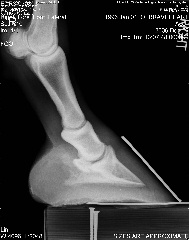

Posted on Saturday, Dec 23, 2006 - 5:11 pm: Right front Left front

| Member: Sunny66 |

Posted on Saturday, Dec 23, 2006 - 5:25 pm: Vet saw right fore, so he blocked right fore heel and he was "sounder" -- still off on left fore after block.Did the navicular series (won't post all of those unless you want to see them) xray guy said (after some prodding from me for info since the vet had left 45 minutes before for an emergency) he didn't see anything that popped out to him as awful. Coffin joint looked squished on both front feet on the OUTSIDE... I think THIS is his problem. Waiting OH so patiently for the vet to review, he promised he'd call me today. |

Posted on Saturday, Dec 23, 2006 - 5:49 pm: The xrays were taken with shoes off... so he's out of alignment with shoes off... so what would it take to get him in line? Anyone want to guess? I've emailed the farrier consultant the xrays... so we'll see what he says too. |

Posted on Saturday, Dec 23, 2006 - 11:30 pm: I'm sorry Aileen! Sometimes it takes pasture rest! Keep at those feet and don't let him get too fat.Hank had a year off while I got his hooves better and he was nqr for that long. Lucky for me I had Muddy Sam for a back up horse, but Hank is my favorite to ride. It was worth the wait and as you know he is now sound and barefoot. There is hope The only thing I see in the X-ray is his toe looks a little long yet, but it all takes time. Good Luck and keep us updated please. |

Posted on Sunday, Dec 24, 2006 - 12:38 am: Aileen, boy, looking at your x-rays compared to Levi,(bute or banamine) and I think Levi looks awful. He is still not really sound walking or trotting, but seems happy, and not really working, so I am hoping we can keep working on getting him straight. Good luck with your boy.suz |